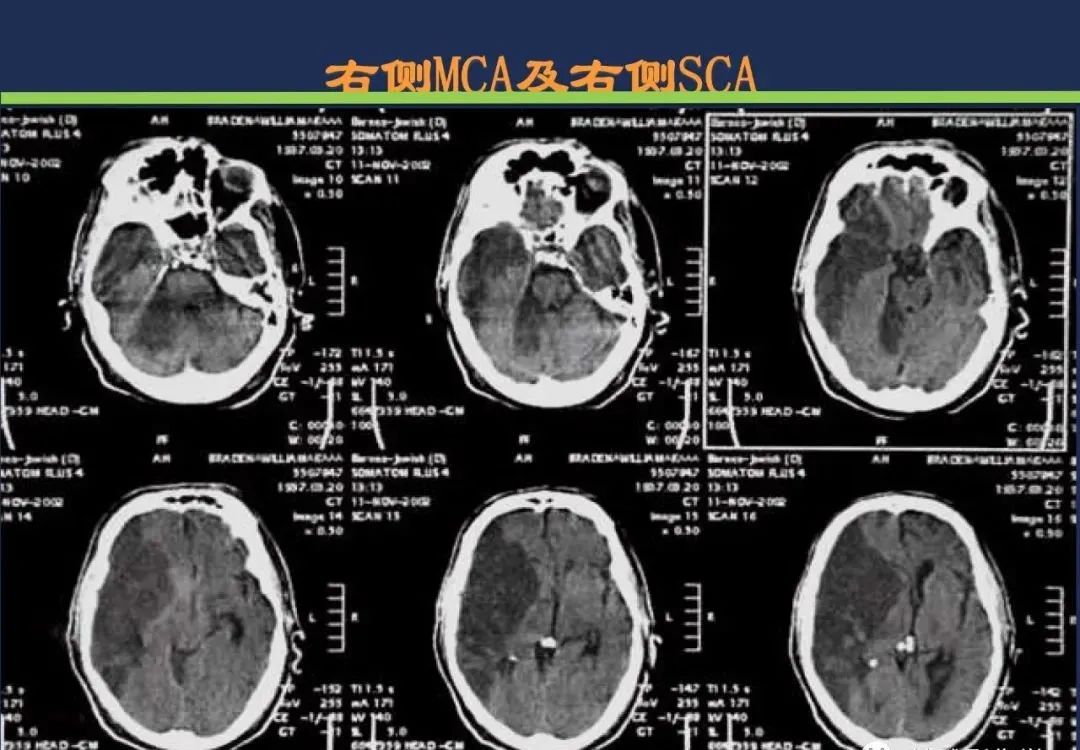

颈内动脉系统梗死颈内动脉大脑中动脉